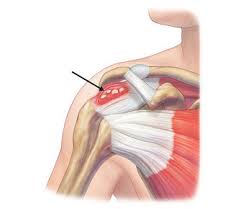

Πρόκειται για εναπόθεση αλάτων υδροξυαπατίτη (επασβέστωση) στην περιοχή της κατάφυσης του υπερακανθίου τένοντα. Είναι το αποτέλεσμα επαναλαμβανόμενων μικροτραυματισμών (υπέρ- χρησης) ή εκφύλισης του τένοντα.

Η ασβεστοποιός τενοντοπάθεια του υπερακανθίου είναι μια συχνή πάθηση του ώμου που προκαλείται από συσσώρευση ασβεστίου μέσα στον τένοντα του μυός υπερακανθίου, ο οποίος αποτελεί τμήμα του στροφικού πετάλου.

Η εναπόθεση αυτή προκαλεί φλεγμονή, έντονο πόνο και περιορισμό της κίνησης του ώμου.